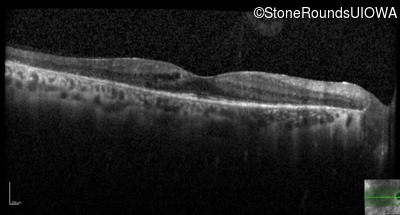

Age at visit: 57 years